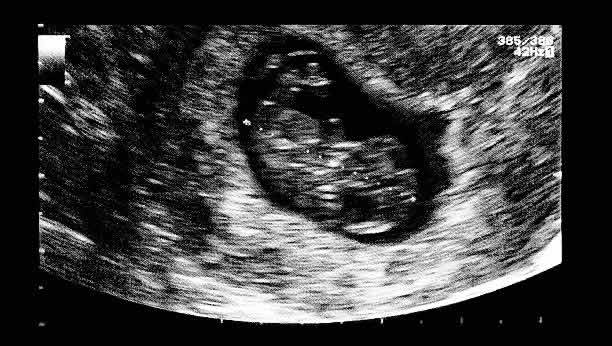

第三代试管婴儿技术,又称胚胎植入前遗传学诊断(PGD),是一种在胚胎植入母体前,对胚胎进行遗传学检测的技术。该技术可以检测胚胎是否携带染色体异常、遗传疾病等,从而提高试管婴儿的成功率,降低出生缺陷的风险。